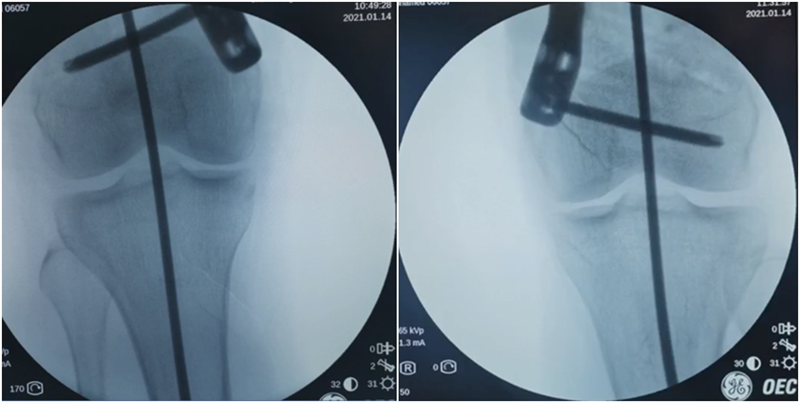

术中发现螺钉松动,截骨端出现坎插迹象。

近端螺钉松开,调整力线,重新固定后,在外侧加小钢板抗旋